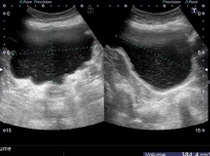

右腎エコー

右腎エコー右水腎症

右水腎症

神経因性膀胱が長期にわたり続いた結果、膀胱尿管逆流症を併発し両側水腎症(腎臓に尿がたまっている状態)を合併しています。この状態が長期間続くと腎機能の増悪に至ります。

写真の症例は、内科で過活動膀胱の薬を処方されている状態でした。

困ったことに、神経因性膀胱の患者さんは、尿意も鈍化しており残尿多量な状態に気づかない患者さんも多いです。